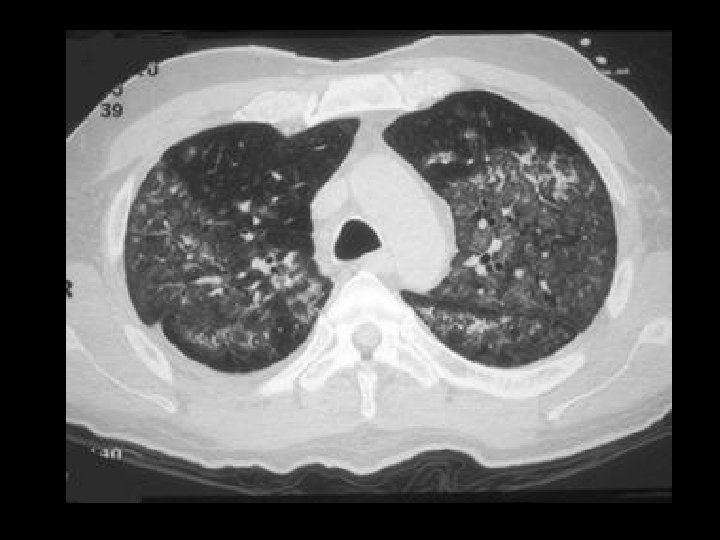

Pulmonary alveolar proteinosis • Findings: – Diffuse ground glass opacities of the secondary pulmonary lobules = “crazy paving” – Scatter thickening of the interlobular septa – Increased risk of Nocardia infection • Rx: BAL • ddx: – NONE! – This is an Aunt Minnie!